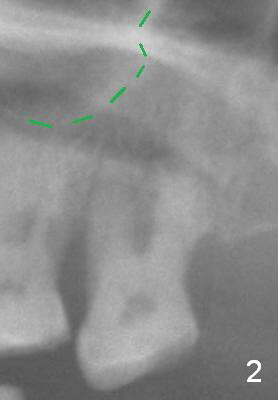

A 53-year-old man (ZB) has history of chronic periodontitis and bruxism. The tooth #18 has been extracted for a few years, while the tooth #15 is going to (Fig.1). Bone height for #15 immediate implant is not a problem (Fig.2-4; green line in Fig.2: sinus floor). After extraction (Fig.5 )socket to be treated with Clindamycin), use starter drill and a 2 mm pilot drill with stopper at 10 mm (Fig.6) on the crest of the septum (Fig.5 S). PA is taken with a parallel pin. Adjust the length accordingly. Subsequent osteotomy will be carried out with drills with stopper at 50 RPM. In brief, the implant does not need to be large. It should be placed as deep as possible (1-2 mm subcrestal mesially and/or distally), since the vertical height in the posterior region is limited. The margin of a cemented abutment is to be slightly subgingival. Use an immediate provisional to close socket gap, while to keep abutment margin from the gingiva. Use Collagen dressing before and after bone graft.